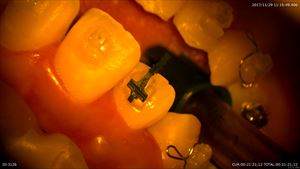

矯正治療

ガタガタが強く2番が口蓋側転位をしています。3番の遠心移動が終わり今日から2番を出します。

デーモンシステム。マイクロでブラケットを正確に。

極細ワイヤーで痛みなし。